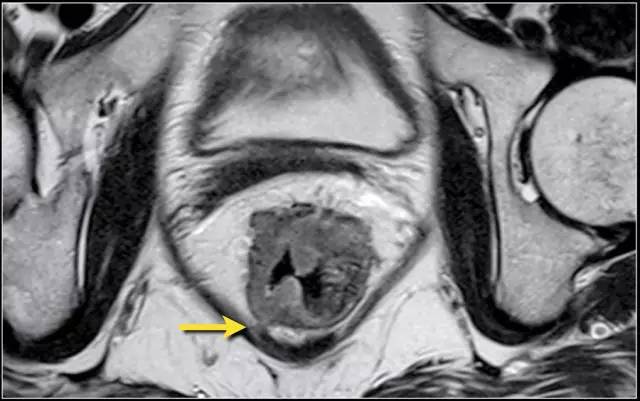

图 6 T3 直肠癌 MRF-,肿瘤浸润直肠系膜,1~4 点钟位置